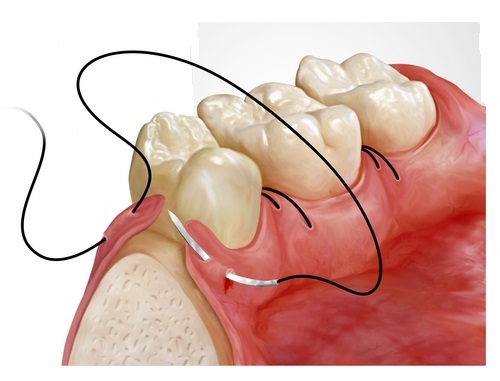

Ağız Cerrahisi

Diş çekimi, gömülü diş operasyonları ve çene cerrahisi uygulamaları.